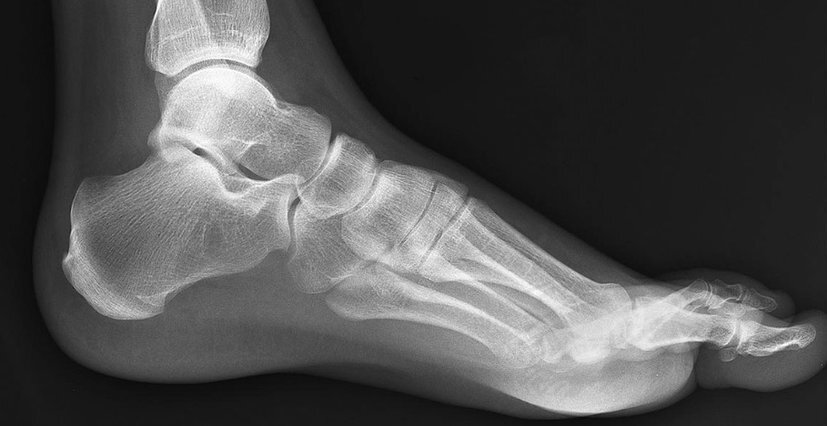

In the event of a broken toe, your doctor will conduct a manual exam to check that the skin around your toe isn’t open and to gauge your levels of swelling, bruising, and tenderness. Imaging scans (x-rays) of your toes from different angles will give them definitive evidence to make a diagnosis of the type of fracture you have incurred and formulate a treatment plan with you.